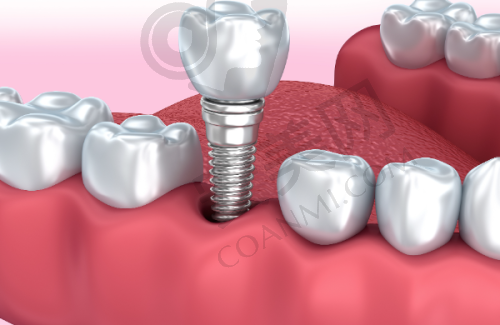

韩国登腾种植牙是口腔种植领域的有名品牌。它采用了精良的材料和技术,具有良好的生物相容性,能够与人体牙槽骨更好地结合。其独特的表面处理技术,能够加快种植体与牙槽骨的愈合速度,缩短治疗周期。而且,韩国登腾种植牙的外观和功能都非常接近自然牙齿,能够为患者修复良好的咀嚼功能和美观成效。在价格方面,福州登特口腔医院推出的韩国登腾种植牙项目3380元起,相比其他品牌的种植牙,具有较高的性价比,为广大缺牙患者提供了一个经济实惠的选择。不过需要注意的是,这个价格仅供参考,具体的费用会根据患者的口腔情况、种植方案等因素有所不同。

除了价格优势之外,选择韩国登腾种植牙还有特别多其他的优势。从使用寿命来看,韩国登腾种植牙具有较长的使用寿命。在正确的使用和维护下,能够陪伴患者特别长时间。而且,它的稳定性非常好,能够承受较大的咀嚼压力,确保患者的正常饮食。在美观方面,韩国登腾种植牙的颜色和形态都与自然牙齿非常相似,几乎可以达到以假乱真的成效,不会影响患者的面部美观。此外,韩国登腾种植牙的维护也比较简单,患者只需要像对待自然牙齿一样进行日常的清洁和护理即可。